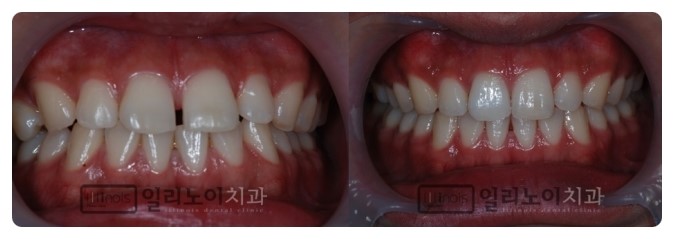

여러 개의 치아개방으로 인한 교정치료의 경우 이 경우 치아 사이의 간격이 커서 앞니뿐만 아니라 치아 사이 전체의 간격이 벌어지게 됩니다. 이 분의 경우 교정치료가 수복치료보다 훨씬 효과적인 치료법이었습니다. 교정치료를 하기로 결정했다면 다음 단계는 벌어진 틈의 원인을 파악하는 것입니다. 치아 사이가 벌어지는 원인에는 여러 가지가 있는데 대표적인 예로는 치주질환, 피개교합, 피개교합, 교합 크기의 부조화 등이 있습니다. 치료를 통해 원인을 제거해야만 재발을 막을 수 있기 때문입니다. 이를 위해서는 정확한 진단 과정이 필요합니다. 대전치과의원 명소는 치아배열 뿐만 아니라 환자의 골격과 치조골 상태를 3차원적으로 분석하여 원인을 규명하고 개개인의 특성에 따른 개별적인 치료 치료계획 단계를 진행합니다. 우리는 계획을 세우고 있습니다. 성공적인 교정치료를 위해서는 얼라이너를 제거할 때 뿐만 아니라 장기적인 결과가 필요하기 때문입니다. 이것은 치열 교정 후 상황이며 간격이 아주 잘 닫힙니다. 대전치과의원 매력 비교 모든 진료가 다 그렇지만 특히 교정치료는 같은 환자가 진단을 받아도 의사마다 경험과 전문성에 따라 치료방법이 달라지는 분야입니다. 그럼에도 불구하고 치료를 시작하실 때는 풍부한 임상 경험을 가진 의료진이 진료를 해주시는 대전의 유명한 치과를 선택하셔야 합니다. 이를 위해서는 다음 섹션을 주의 깊게 비교할 필요가 있습니다. 연세고운스마일은 연세대학교 치과병원에서 정식 수련을 받은 교정과 전문의와 대표원장이 진료하고 있습니다. 첫 번째. 교정전문의는 전체 치과의사 중 1~2% 정도에 불과하며, 이러한 전문의는 대학병원 등 분야에서 전문교육을 받고 보건복지부 고시를 통과한 의사에게만 수여된다. 교정치료에 대한 집중적인 수련을 받았고 많은 임상시험을 거쳐왔기 때문에 아마도 더 믿을만 할 것입니다. 둘째, 원장님을 대신하여 교정치료를 직접 진행하는 곳인가요? 치료의 특성상 초기에 진단과 계획을 수립한 의사가 끝까지 주치의 역할을 하는 것이 좋습니다. 급여는 필연적으로 떨어질 것입니다. 유명한 대전치과의원에서는 대표 원장님이 모든 교정치료를 유급의사 없이 진행하고 있어 의료진 교체 없이 안전하게 진료를 받으실 수 있습니다. 제삼. 정확한 진단 과정에서 환자에게 가장 적합한 치료 계획을 세울 수 있습니다. 연세고운스마일은 치아의 배열뿐만 아니라 균형 잡힌 입술 라인과 얼굴 특징의 변화까지 고려한 심미적 치료 계획을 제시하는 디지털 진단 시스템으로 구축되고 있습니다. 네번째. 비용이 많이 드는 치료이기 때문에 부담을 느끼시는 분들이 많습니다. 유명한 대전치과에서는 다양한 미용기기를 합리적인 가격으로 준비하고 있습니다. 특히 첫 달부터 치료가 끝날 때까지 치료비 전액을 분할납부하는 제도로 비용을 걱정하며 치료기간을 미루는 일이 없도록 돕고 있습니다. 연세고운스마일은 숙련된 의료진과 체계적인 진료과정, 세심한 사후관리를 통해 다양한 부정교합 증상을 가진 환자들의 밝고 환한 미소를 만들어 드리고 있습니다. 갤러리아 백화점 맞은편에 위치해 평일 바쁜 현대인들을 위한 나이트 케어도 제공한다.궁금하신 사항은 www.misodj.com 으로 편하게 문의주세요 대전 연세궁미소치과 대전, 연세궁미소치과의원, 연세궁미소치과의원, 교정과, 교정전문의, 무발치, 돌출교정, 맑은치과 연세대학교 의료진 www .misodj.com 대전광역시 서구 대덕대로 203 연세고운미소치과 5층